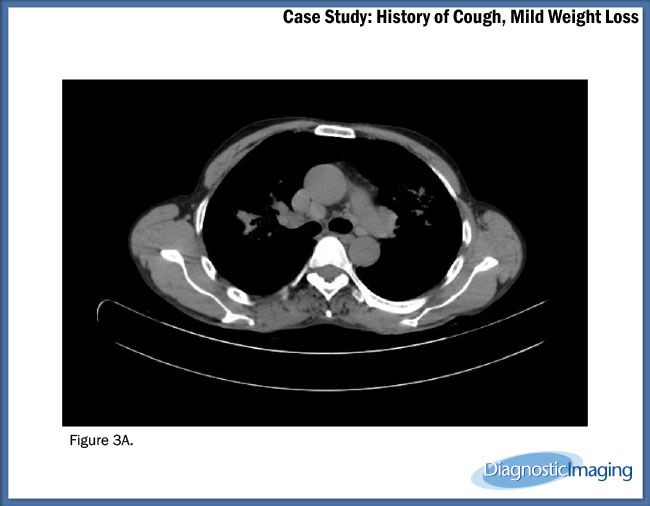

Case History: 49-year-old patient presented with history of cough; mild weight loss was noted.

Case History: A 49-year-old patient presented with history of cough; mild weight loss was noted.